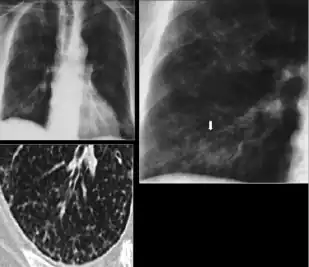

3. Nodule with poorly defined margins - Round density within the lung parenchyma, also called a tuberculoma. Nodules included in this category are those with margins that are indistinct or poorly defined (tree-in-bud sign[3]). The surrounding haziness can be either subtle or readily apparent and suggests coexisting airspace consolidation.

Chest x-ray showing nodule with margins that are indistinct or poorly defined (tree-in-bud sign) in post-primary pulmonary TB.

5. Other—Any other finding suggestive of prior TB, such as upper lobe bronchiectasis. Bronchiectasis is bronchial dilation with bronchial wall thickening.

Chest x-ray showing course bronchiectasis of the lungs post-primary pulmonary tuberculosis.